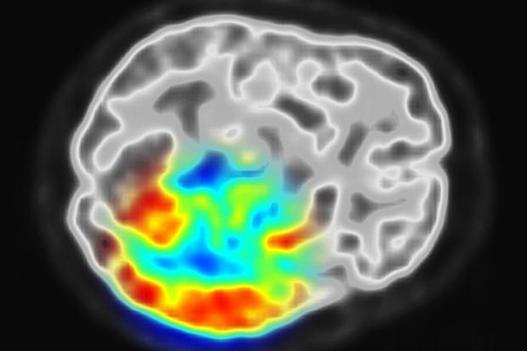

Researchers have just made brainprint biometrics far more accurate, identifying you by how you think